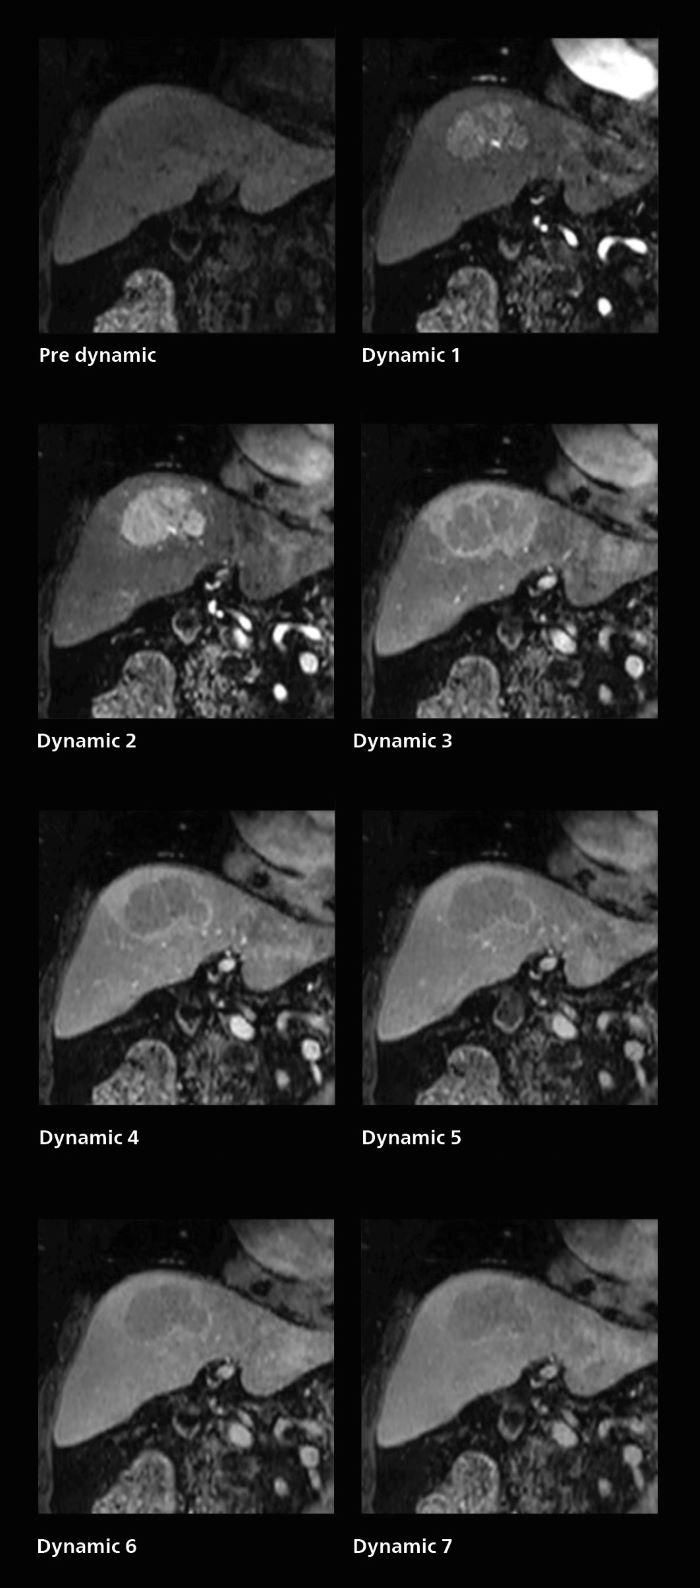

3D MRI of breast cancer

Scanning was performed with two different voxel sizes. AI enabled volume MRI allows image reconstruction in other directions. Biopsy revealed invasive ductal carcinoma in this patient. Performed on Elition X.

Fast AI-enabled MRI of breast cancer: comparing 3D acquisitions with 0.75 mm and 0.6 mm isotropic voxels.

Fast AI-enabled MRI of breast cancer: comparing 3D acquisitions with 0.75 mm and 0.6 mm isotropic voxels, mobile one

Fast AI-enabled MRI of breast cancer: comparing 3D acquisitions with 0.75 mm and 0.6 mm isotropic voxels, mobile two

• ExamCard for 0.7 mm isotropic, 2:09 min, acceleration factor 7.5

• ExamCard for 0.6 mm isotropic, 3:37 min, acceleration factor 8